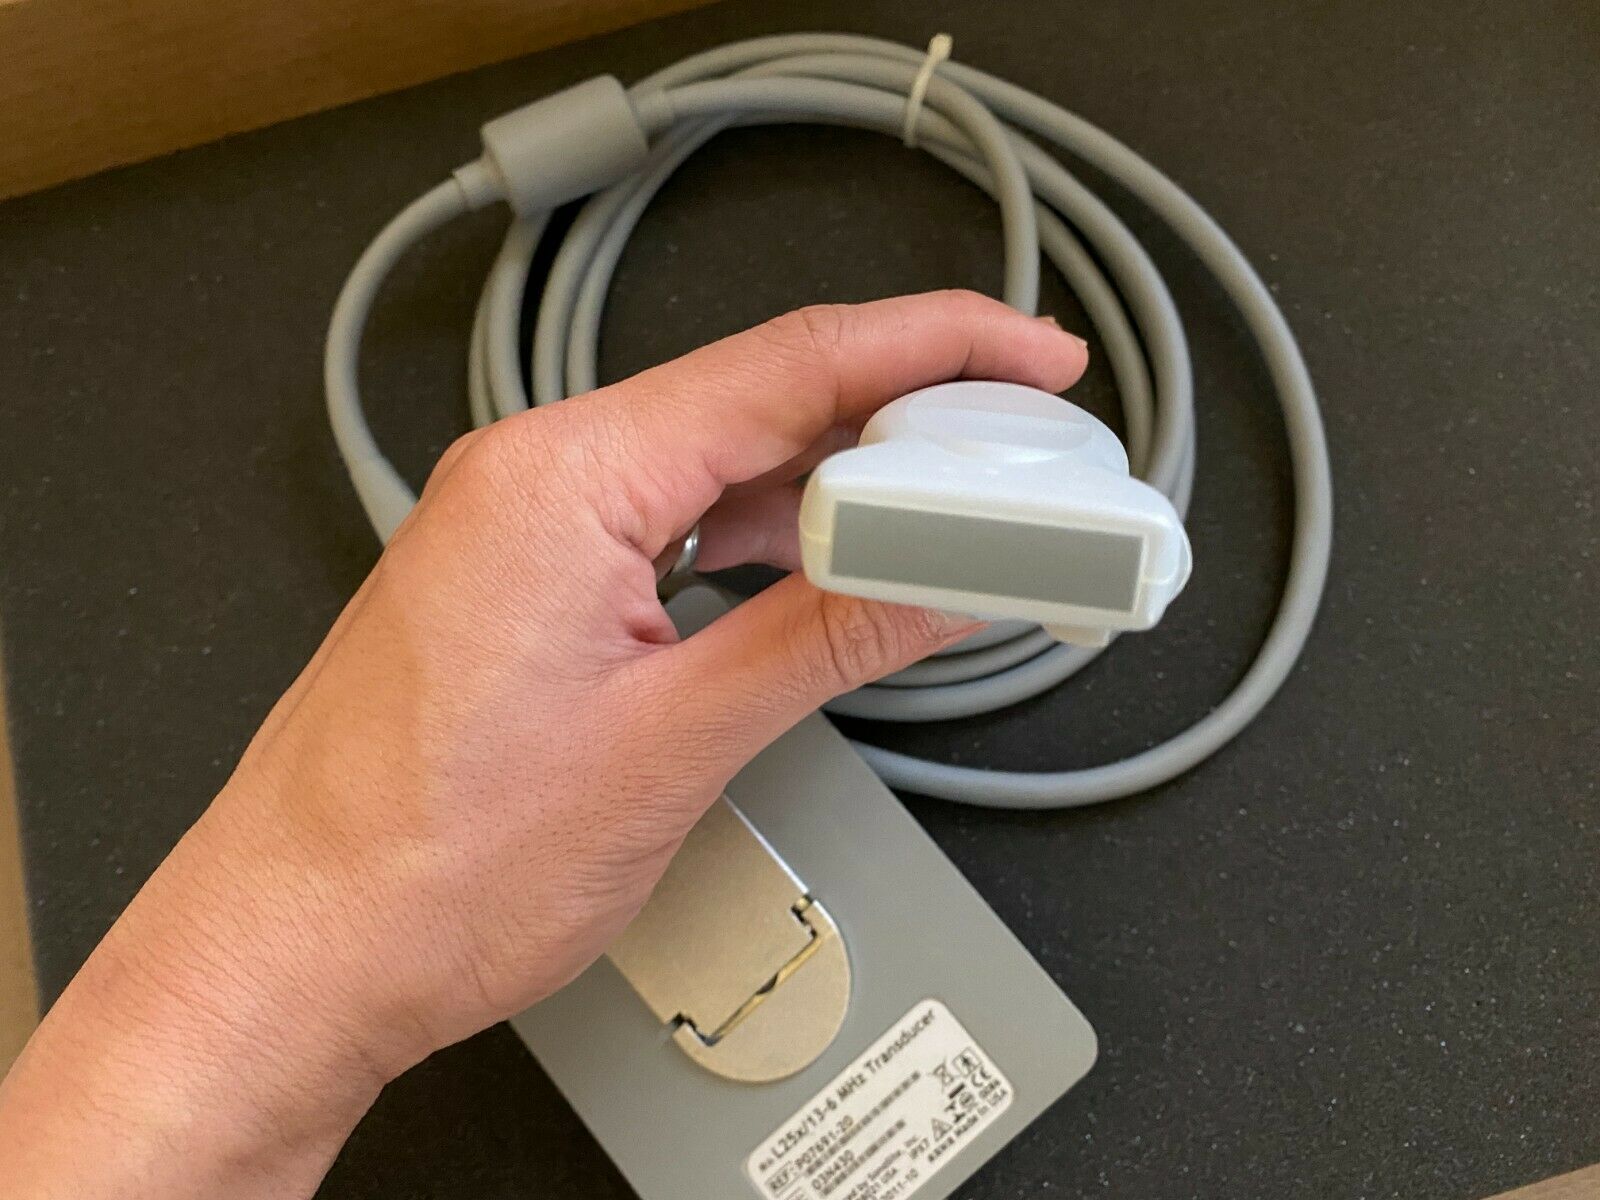

SONOSITE L25X LINEAR FOR M-TURBO EDGE S - Top-Notch Ultrasound Probe

SONOSITE L25X LINEAR FOR M-TURBO EDGE S-NERVE TRANSDUCER - Ultrasound Probe

The SONOSITE L25X LINEAR FOR M-TURBO EDGE S is a premier ultrasound transducer designed to provide high-quality imaging for a variety of clinical applications. This specialized probe is compatible with the SONOSITE M-TURBO EDGE system, a leading point-of-care ultrasound device that delivers exceptional image clarity and reliability. Whether you are in emergency medicine, regional anesthesia, or vascular procedures, the SONOSITE L25X LINEAR provides precise and reliable results every time.

Designed with advanced technology, the SONOSITE L25X LINEAR FOR M-TURBO EDGE S offers a frequency range that is optimal for superficial imaging, aiding healthcare professionals in obtaining detailed and accurate images. The probe's ergonomic design ensures ease of use during extended scanning sessions, reducing operator fatigue. SONOSITE, a brand known for its innovation and quality, ensures that every detail of the L25X LINEAR is tailored to meet the high demands of modern medical environments.

In addition to its superior imaging capabilities, the SONOSITE L25X LINEAR FOR M-TURBO EDGE S is built to withstand the rigors of everyday clinical use. Its durable construction means it can handle frequent cleaning and disinfection processes essential in maintaining hygiene standards in medical settings. Investing in this ultrasound probe not only enhances diagnostic accuracy but also ensures a reliable performance that stands the test of time.

The SONOSITE L25X LINEAR FOR M-TURBO EDGE S is also known for its quick-and-easy setup, which saves valuable time in fast-paced clinical settings. Furthermore, it offers seamless integration with the SONOSITE M-TURBO EDGE system, providing a user-friendly experience that complements the workflow of healthcare professionals. This leads to improved patient care and optimized clinical operations.

For any healthcare facility looking to enhance its ultrasound imaging capabilities, the SONOSITE L25X LINEAR FOR M-TURBO EDGE S is a worthy investment. Its high-resolution imaging, durability, and user-oriented design make it a standout choice in the market. With the SONOSITE L25X LINEAR, clinicians can perform accurate diagnoses, carry out intricate procedures with confidence, and ultimately, improve patient outcomes. Don't miss out on the opportunity to advance your practice with this exceptional ultrasound probe.